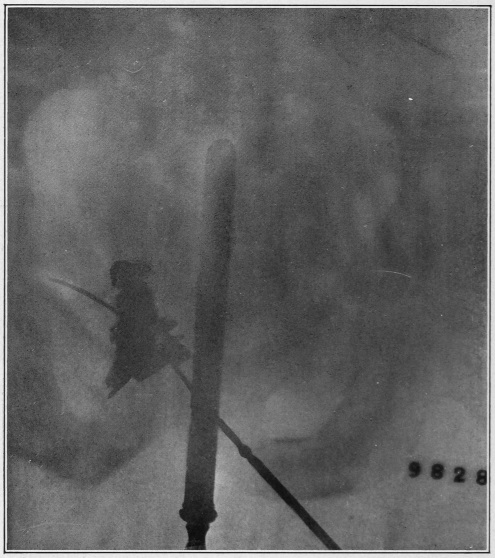

Nine Radiograph Illustrations Showing Mucus Channels and Cavities200

CHAPTER V.

Rebellion of our outraged Internal Economy.

The small intestine is that portion of the alimentary canal which begins at the stomach and ends at the large intestine. Its usual length is twenty feet. The diameter, which at the upper portion (duodenum) is two inches, gradually becomes less, until at the lower end it is but one inch.

Now, the length of the inner coat of this small intestine—the mucous membrane—is about double that of the intestine itself. Think of wearing a coat twice as long as yourself! How do you think this is accomplished in the case of the muscular tube under con­sid­er­ation? Well, Nature, having a most peculiar function to perform, has thrown this mucous coat or tube into a thousand folds (valvulæ conniventes, or “winking valves”). These folds form valves, occupying from one-third to one-half the circum­ference of the bowel. The greatest width of each fold is at the center, where it measures from a quarter to half an inch. Over this great expanse of mucous membrane we find studded ten million five hundred thousand intestinal villi, whose office it is to absorb the food substances in their passage through the canal.

Fig. 9.

Stomach, liver, small intestine, etc. (Flint.) 1, inferior surface of the liver; 2, round ligament of the liver; 3, gall-bladder; 4, superior surface of the right lobe of the liver; 5, diaphragm; 6, lower portion of the œsophagus; 7, stomach; 8, gastro-hepatic omentum; 9, spleen; 10, gastro-splenic omentum; 11, duodenum; 12, 12, small intestine; 13, cæcum; 14, appendix vermiformis; 15, 15, transverse colon; 16, sigmoid flexure of the colon; 17, urinary bladder.

Those that have observed the anatomical illustrations of the small intestines must have been struck by their apparently inextricably tangled convolutions. In life, these convolutions are constantly changing their locations, as though they were a mass of worms.

Fig. 10.

The cæcum, dorso-mesial view, showing the ileum-side of the ileo-cæcal valve, and the beginning of the three muscular ribbons. (Gerrish.)